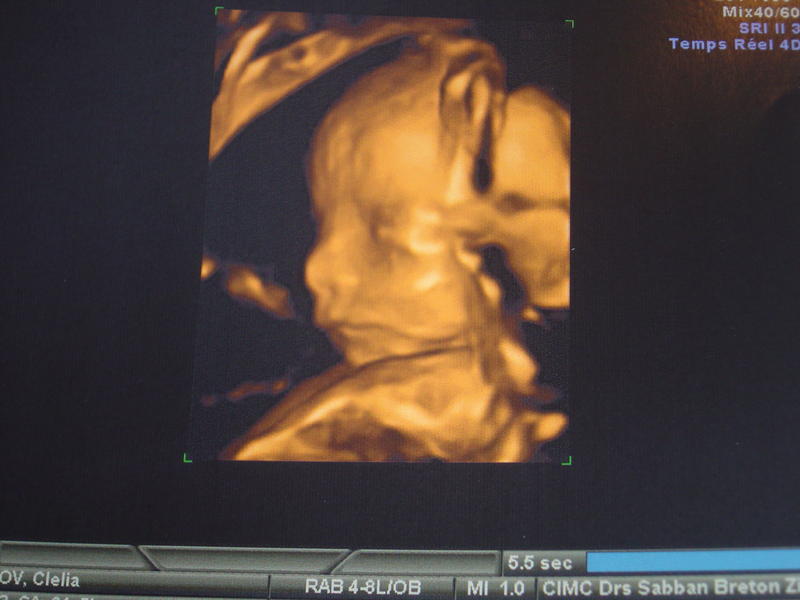

Alors moi écho faite , tout vas bien et c'est ... UNE FILLE !!!!

clélia: félicitation ma belle!! une nénette c'est top!!